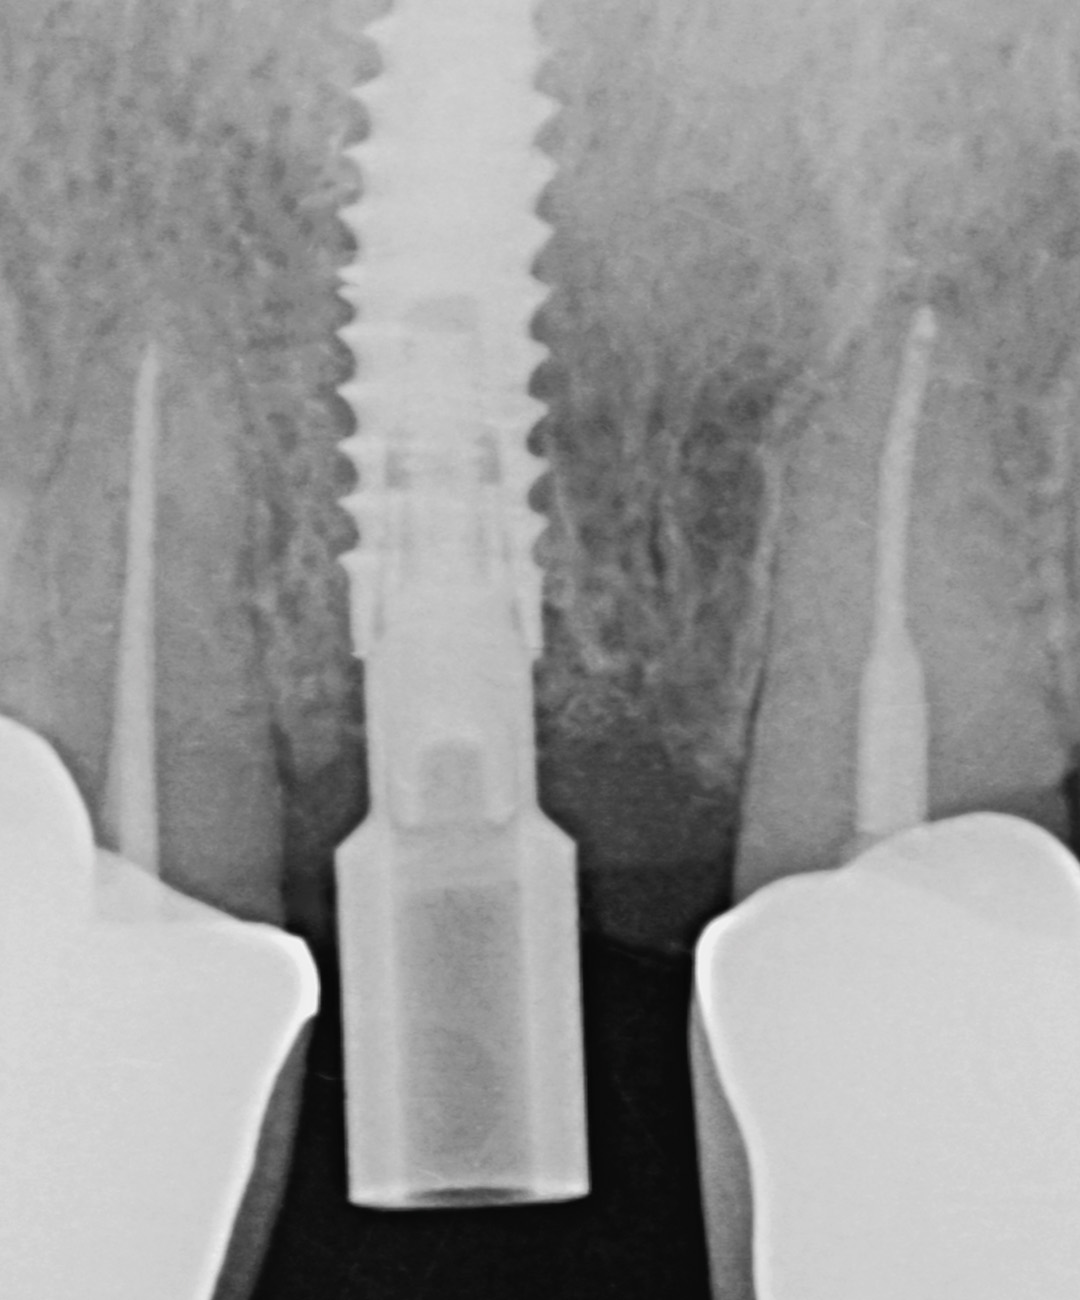

Four months post-placement, the implant site exhibited stable soft tissue contours and full graft integration. A screw-retained lithium disilicate crown was delivered and bonded to a customised anodised titanium abutment. Radiographs confirmed excellent osseointegration and bone preservation. Post-operative care included chlorhexidine 0.12% gel application twice daily for 14 days. The patient expressed high satisfaction with the aesthetic result, and no recession or tissue shrinkage was observed during the healing period.

Surgical healing was uneventful and the patient reported no pain or discomfort. Papillae remained healthy and filled the embrasures completely. A final zirconia restoration was ultimately placed, designed to slightly alter the over-contoured emergence profile from the exocad software. This simplified the fitting protocol and further prevented the collapse of the hard or soft tissue during the final healing phase.